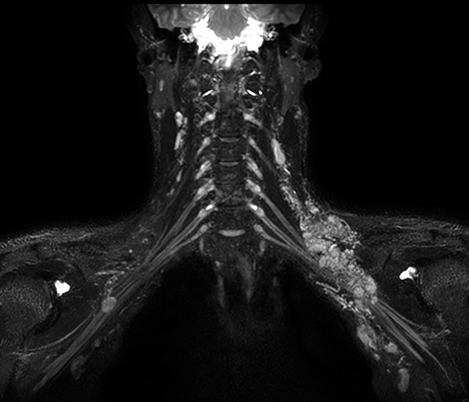

70% of radiologists consider neuro indications to be challenging, mostly due to a lack of appropriate imaging and visualization techniques¹. Philips aims to provide the best possible diagnostic clarity and treatment guidance for all patients with neurological disorders.

By leveraging our dStream digital platform, this year, we are introducing, a set of novel imaging and visualization strategies. These may empower you to resolve complex neuro questions with more certainty, as well as unlock new neuro territories in advanced Neurofunctional applications. This is a key step towards elevating neuro diagnostics and ultimately touching more lives with MR imaging.

Black Blood

Eramse Hospital, Belgium

Black Blood MRI imaging of HIV patient with brain vasculitis

Black Blood imaging helped in suggesting the diagnosis and choosing the treatment.